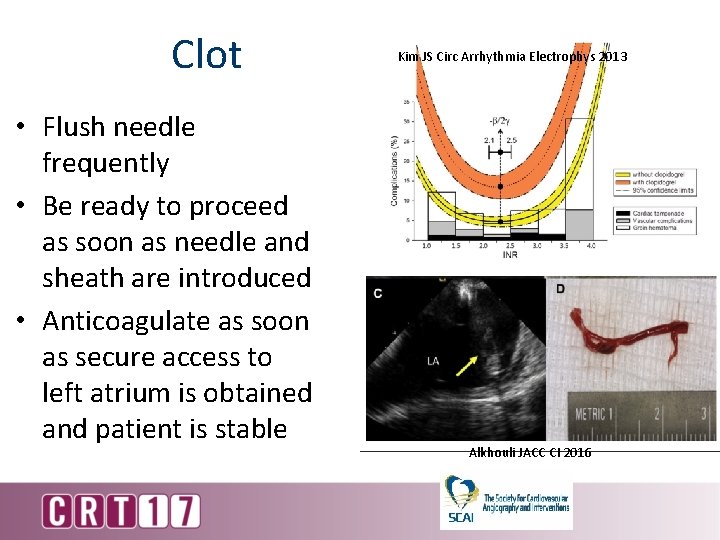

Clot • Flush needle frequently • Be ready to proceed as soon as needle and sheath are introduced • Anticoagulate as soon as secure access to left atrium is obtained and patient is stable Kim JS Circ Arrhythmia Electrophys 2013 Alkhouli JACC CI 2016